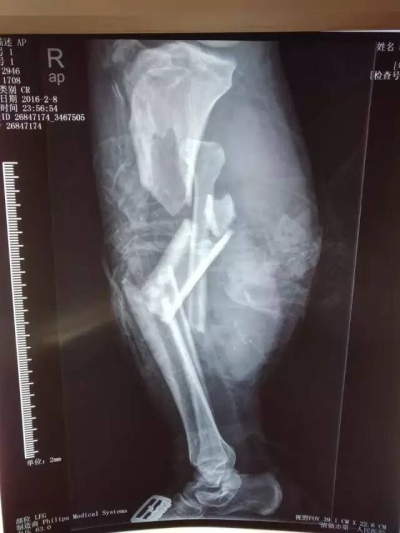

9点50分,罗xx,男,30岁,双小腿压榨伤。经转清镇市和贵阳两个医院后,于伤后约6小时急诊就诊于我院。入院后,诊断为:1.创伤失血性休克,2.右腘动静脉、胫神经、腓总神经损伤,3.右胫后动脉损伤,4.右胫腓骨开放性粉碎性骨折,5.右腓骨头骨折脱位,6.右小腿广泛皮肤软组织潜行剥脱伤,7.右大腿皮肤软组织挫伤,8.左胫腓骨粉碎性骨折。由于伤者伤情严重,又是在伤后6小时才辗转来到我院,延误了救治时间,失血3500ml,患者面临截肢的危险,伤情已经危及生命。时间紧迫刻不容缓,作为显微外科技术名列全省领先地位的贵阳市显微外科中心,我院立即开通绿色通道,骨三科值班医护人员在学科带头人宋开芳主任的指示下,积极补液输血,纠正患者休克,维持生命体征平稳,作好术前一切准备工作;检验科以最快速度为患者作了术前化验检查,输血科为患者作了交叉配血并准备了充分的血液供应;麻醉师唐恒、龙莎快速稳妥地为患者进行了麻醉。杨颇副主任和姜昱林医师从初二上午10时上手术台,历时12小时的手术,术中输血3000ml,重建了肢体血液循环,挽救了患者的肢体。目前,患者生命体征平稳,肢体血液循环稳定。经骨三科、麻醉手术科、输血科、检验科、总务科等相关科室有效积极的配合,成功对患者进行了救治。